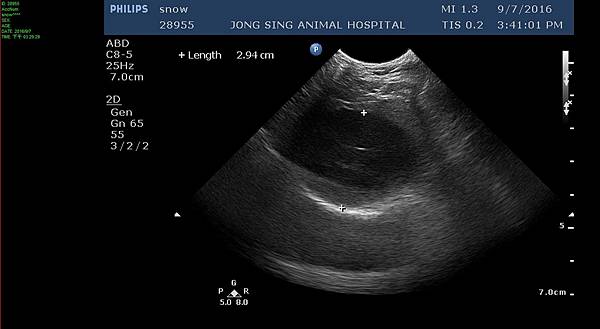

今天做的檢查有血檢和超音波

超音波底下看,囊肝的囊泡也變嚴重了

雖然這個角度是2.94cm,但最長能量到3.3cm.gif)

也疑似有壓迫到膽囊